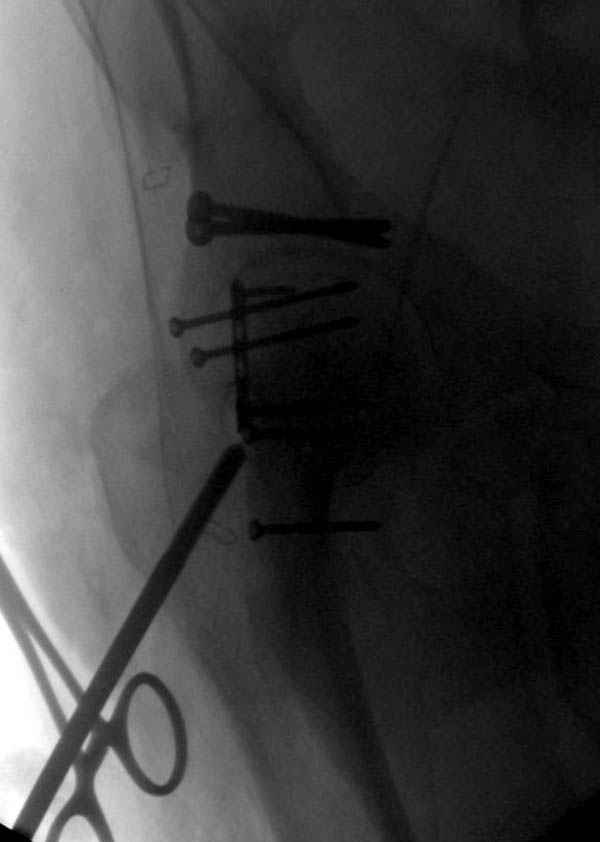

На седьмой день зафиксирован перелом ацетабулума через задний доступ. Перед операцией для профилактики DVT, IVC фильтер, также получает Lovenox.

Там множество обычных 2.7 мм шурупов, потом идет фиксация основными пластинами.

В нашем протоколе в день операции делаем допплеровскую проверку сосудов, и в координации с сосудистыми хирургами установку фильтра до начала нашей операции, современные фильтры временные, можно удалить через несколько месяцев.

Полную нагрузку разрешаем в 12 недели, хотя движения в суставе с первых дней.

Снимки здесь....